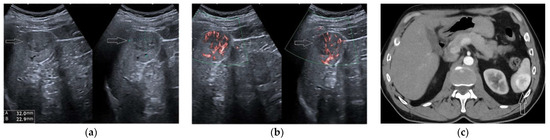

2.5. Hematoma and Abscess

2.6. Infarcts

2.7. Solid Lesions